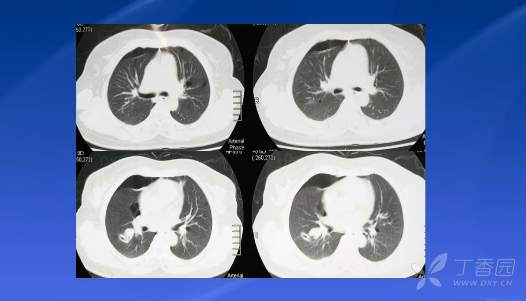

病例 1. 23 岁女性妊娠晚期呼吸困难+胸部 CT 弥漫性囊性病变

病例 2.一例以咳嗽为表现的弥漫性囊性病变

病例 3. 一例慢性弥漫性肺部囊性病变

病例 4. 一例辗转多家医院的反复气胸的BHD